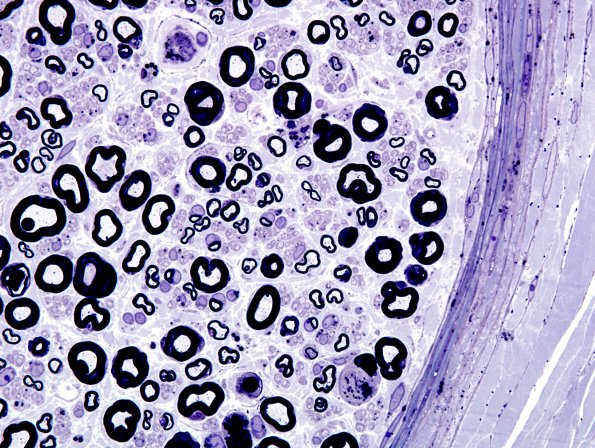

Washington University Experience | PERIPHERAL NEUROPATHY | 17 TOXIC NEUROPATHIES | Amiodarone | 1A9 Amiodarone (Case 1) Plastic 7

The perineurium and epineurial vasculature are involved by osmiophilic inclusions. (plastic section)